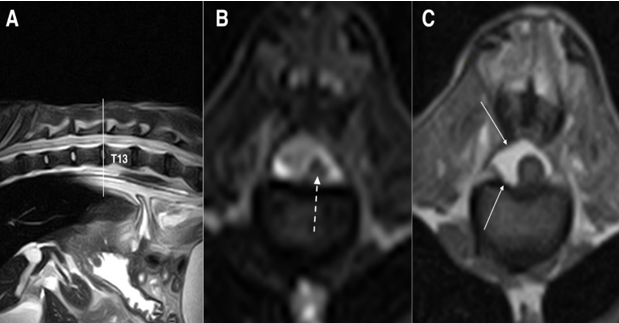

Figure 5: SE T1 weighted images on sagittal (A) and transverse planes (B and C). Disc protrusions in the space T13-L1 (white arrow) and L1-L2 (dashed arrow), without spinal cord compression at both sites (B and C). The black asterisk (B) highlights the epidural fat that replaced the spinal canal, while the white asterisk (C) shows the enlarged subarachnoid space

After another 16 months, the patient showed worsening hind limb paresis; however, it was still ambulatory. Severe atrophy of the hind limb muscles was also observed. Due to the onset of severe megacolon that was not responsive to medical and dietary treatments, and severe chronic kidney failure, the owner decided to euthanize the animal. A new MRI for diagnostic purposes was performed, and the thoracolumbar spinal cord was collected for histopathological examination.

The MRI scan confirmed the presence of the protrusions already detected in previous imaging studies. Disc protrusions were still low and were not significantly compressive, and the spinal cord had a normal signal; however, the reduced diameter and intra-canal free space were mostly filled with epidural fat ventrally and laterally on the left side of the spinal cord. These findings were confirmed using necropsy (Fig 6A). The segment of the spinal cord between T5 and L7 (Fig 6B) was histopathologically analyzed after fixation in 10 % neutral buffered formalin, followed by paraffin embedding and routine staining of the slides using hematoxylin and eosin.